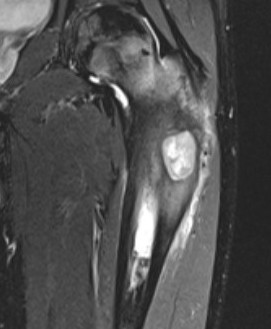

MRI

Long bone

- more common meta-diaphyseal

- large faintly radiolucent lesion

- thin reactive rim

- may be expansile